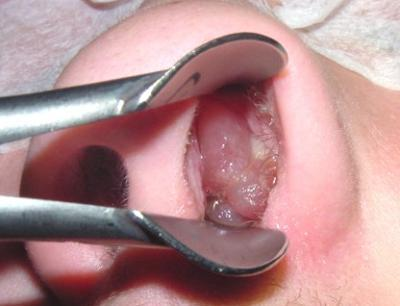

Рисунок: полипы носа